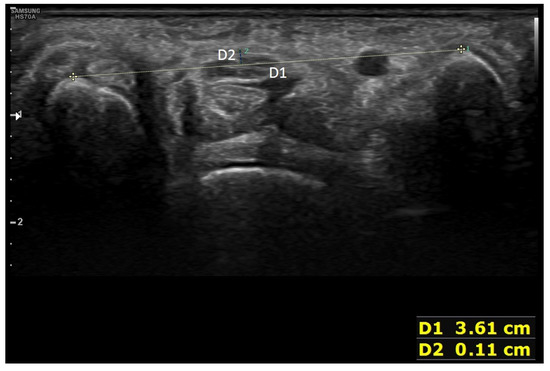

| 11–1. Connecting the top of the scaphoid and the pisiform with a line | 1 | 0.76 ± 0.43 | |

| 11–2. Measuring the vertical distance between the line connecting the top of the scaphoid and the pisiform and the flexor retinaculum | 1 | 0.64 ± 0.48 | |